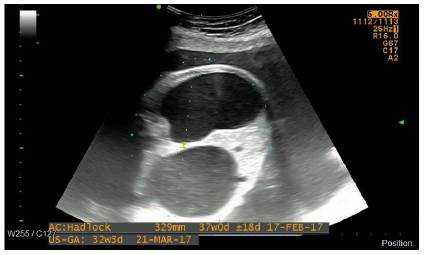

En una ecografía de seguimiento realizada en la semana 31, además se logra evidenciar en el mediastino, una imagen anecoica no vascularizada al Doppler color, con relación a dilatación esofágica en el tercio distal, la cual se asoció a polihidramnios, con lo que se hizo una impresión diagnóstica de atresia esofágica asociada (Figuras 3 y 4).

Hacia la semana 33 de gestación, ingresa nuevamente la paciente al servicio de urgencias de Ginecología y Obstetricia, con amniorrea evidente y en trabajo de parto en fase latente. Se realiza cesárea de urgencias por estado fetal no tranquilizador según reporte de monitoría fetal electrónica. Se recibe recién nacido femenino Ballard para 33 semanas, con peso de 1.780 g considerado adecuado para edad gestacional, con adaptación conducida y posterior falla ventilatoria, requiriendo intubación orotraqueal. En el examen físico se evidenció implantación baja de las orejas, arteria umbilical única, abdomen distendido, ano imperforado con fístula recto vestibular y genitales femeninos externos normoconfigurados. Es trasladada a unidad de cuidados intensivos neonatales, en donde se realiza radiografía de tórax y abdomen (Figura 5), la cual muestra arcos costales derechos fusionados, hemivértebras y ausencia de gas en cámara gástrica, considerando una atresia esofágica tipo 1. Dados los antecedentes prenatales, los hallazgos clínicos e imagenoló-gicos, se considera una asociación VACTERL y se decide completar el estudio de posibles anormalidades asociadas, realizando ecocardiograma, ecografía transfontanelar, ecografía renal y vías urinarias, todas reportadas normal. Fue llevada a su primera cirugía a las 48 horas de vida, donde se le realizó gastrostomía, colostomía y resección de membrana duodenal. A los 11 días de vida se realizó inicio del estímulo enteral trófico por gastrostomía. En segundo tiempo quirúrgico, 34 días después, se realizó toracotomía derecha y anastomosis término terminal esofágica.

En una serie de 114 casos reportados por Ladd y Swenson se describe la incidencia de la asociación entre atresia esofágica y atresia duodenal en aproximadamente 5 % de los casos de la asociación VACTERL, y es aún más baja la incidencia asociando además el ano imperforado, como lo es en el caso presentado 12. Teóricamente el diagnóstico de la atresia esofágica con fístula traqueoesofágica, atresia duodenal y malformación anorrectal puede realizarse de manera prenatal, con confirmación con estudio radiológico de tórax y abdomen en el neonato; sin embargo, hay gran dificultad especialmente cuando se trata de una atresia esofágica pura 15; en nuestro caso se reporta una atresia esofágica tipo 1. Identificamos varios casos en la literatura que se realizan en diagnóstico prenatal de atresia esofágica tipo 1 con atresia duodenal 16-19; no obstante, solo en uno, así como en nuestro caso, se logran evidenciar todos los hallazgos eco-gráficos típicos, que incluyen polihidramnios, dilatación esofágica distal y signo de la doble burbuja intraabdominal 17.